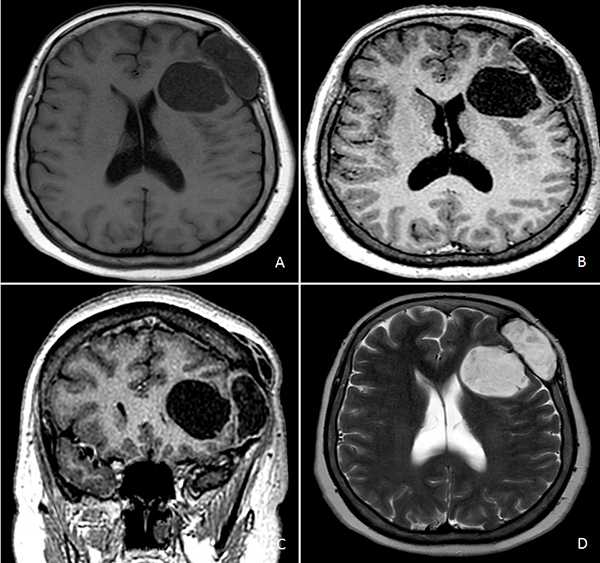

Figura 2.

RM de cerebro. A) Secuencia T1 sin contraste endovenoso. B) y C) Secuencia T1 con contraste endovenoso. D) Secuencia T2.

Resonancia magnética (RM) de encéfalo con contraste endovenoso evidenció una lesión heterogénea, predominantemente hipointensa en secuencia T1, hiperintensa en T2, heterogénea e isointensa con respecto al parénquima cerebral en Flair (Fluid attenuated inversión recovery), con escasas áreas de restricción en la secuencia difusión (DWI) y realce fino periférico tras la administración de contraste (Figura 2). Se observó efecto de masa leve con colapso de asta frontal de ventrículo lateral homolateral. Se realizó una angiotomografía de encéfalo para valorar la vascularización adyacente de la masa y descartar anomalías vasculares, siendo negativa para las mismas.